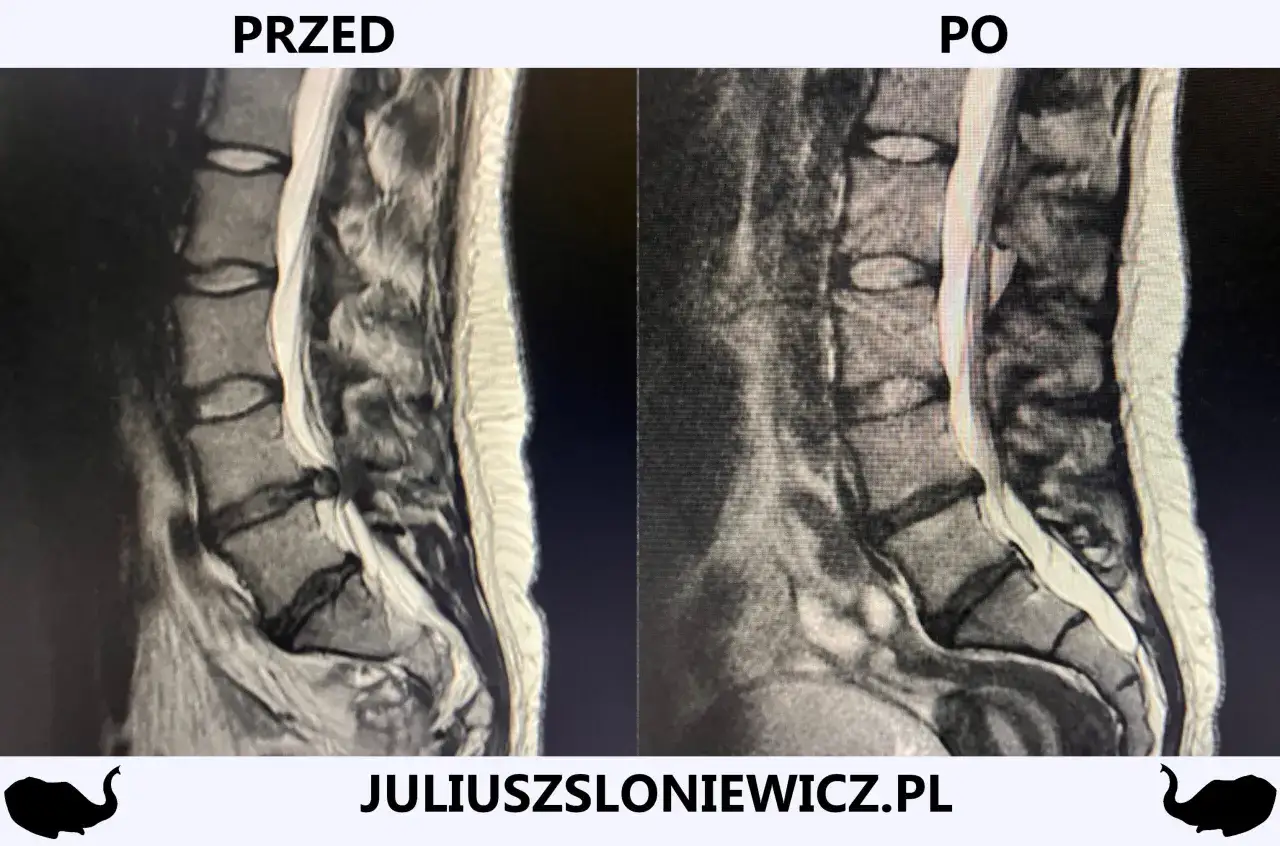

Rezonans magnetyczny (MRI) jako złoty standard w diagnostyce: Co pokaże badanie?

Jeśli lekarz uzna to za konieczne, w celu potwierdzenia diagnozy i precyzyjnego określenia przyczyny ucisku na nerw, zleci badania obrazowe. Rezonans magnetyczny (MRI) kręgosłupa lędźwiowego jest uznawany za "złoty standard" w diagnostyce rwy kulszowej. Dlaczego? Ponieważ MRI doskonale uwidacznia tkanki miękkie krążki międzykręgowe, więzadła, nerwy co pozwala dokładnie zobaczyć, czy i gdzie występuje przepuklina, stenoza czy inny ucisk na korzenie nerwowe. Tomografia komputerowa (CT) i zdjęcia rentgenowskie (RTG) są również wykorzystywane, ale głównie do oceny struktur kostnych kręgosłupa, np. w przypadku podejrzenia zmian zwyrodnieniowych czy kręgozmyku. Nie są one tak skuteczne w obrazowaniu dysków i nerwów jak MRI.